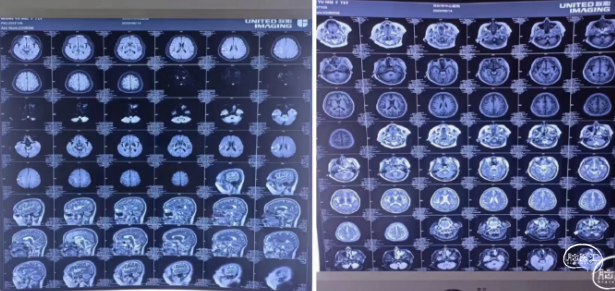

MRI(2023.06.14/外院)

MRI (2023.06.25/本院)

右侧大脑半球梗死灶较前增加

MRI(2023.06.25/本院)